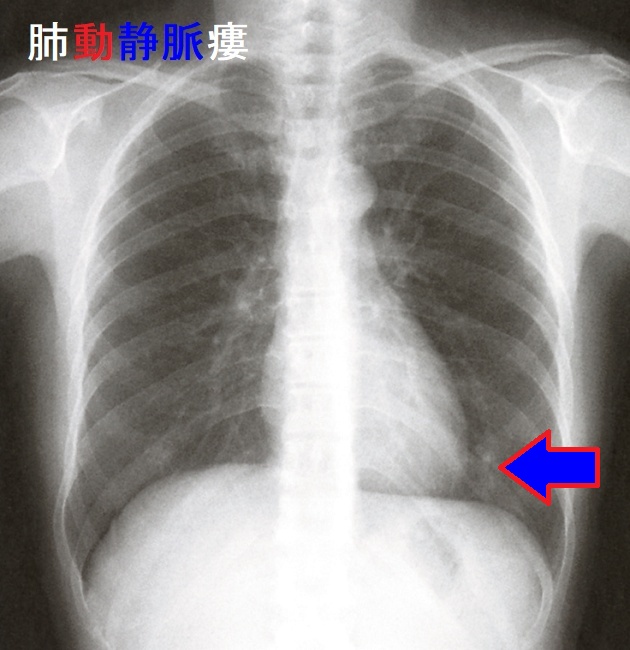

甲状腺癌肺転移により肺動静脈瘻(pulmonary arteriovenous fistula)ができると、

- 肺胞での酸素・二酸化炭素交換をすることなく、肺動脈から肺静脈へのシャントができるため、呼吸困難・チアノーゼ・多血症・バチ指、右心不全、脳虚血

- 肺というフィルターを介さずに、静脈から動脈に血栓・菌が通り抜けて脳に行き、脳梗塞・脳膿瘍

あるいは、菌が心臓に行き、感染性心内膜炎

- 肺動静脈瘻の血管壁は脆く、破裂して喀血・血胸

(MedTimes1979;107:87―92.)

[Am J Surg. 1964 Sep;108:416-8.][N Engl J Med. 1959 Apr 30;260(18):901-7.]

欧米において肺動静脈瘻の10-70%は遺伝性で、遺伝性出血性毛細血管拡張(オスラー・ウェーバー・ランデュ病)に合併しますが、日本では10-20%程度です。(日本臨床 別冊呼吸器症候群Ⅱ:374-378,2009)

大きな無症候性肺動静脈奇形と結節性甲状腺腫・甲状腺乳頭癌が合併して、甲状腺乳頭癌肺転移との鑑別を要した報告があります。[Indian J Nucl Med. 2020 Oct 21;35(4):326–329.]

肺動静脈瘻自体は、無症状時、胸部エックス線写真や胸部単純CT画像から偶然、発見されることが多い。しかし、喀血、脳梗塞・脳膿瘍の危険性が高いため、3 mm 以上は治療適応。経カテーテル塞栓術。